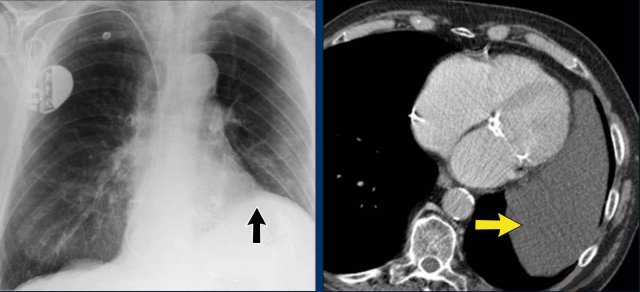

Pericardial cyst

Pericardial cysts are benign lesions that are anatomically connected to the pericardium and typically contain clear, serous fluid.

The majority of pericardial cysts are located in the anterior cardiophrenic angle, more frequently on the right side.

However, they may also be identified more superiorly, within the pericardial recesses at the level of the proximal ascending aorta and main pulmonary arteries.

Most patients remain asymptomatic.

On chest radiography, a pericardial cyst may mimic an elevated left hemidiaphragm (black arrow).

However, CT more clearly demonstrates a fluid-filled cystic lesion contiguous with the pericardium (yellow arrow).